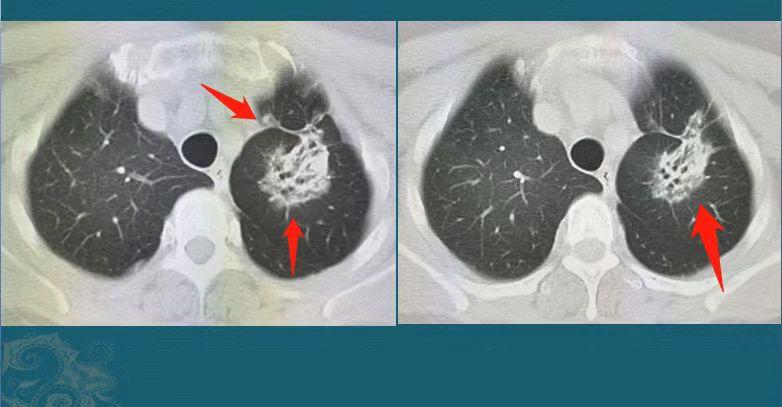

我们举例说明:

这是一位51岁女士,偶尔胸痛,没有其他症状,但CT发现右下肺脊柱旁不规则实性肿块,长径3.3cm,边缘可见胸膜凹陷征,下缘与胸膜广泛接触,手术病理是浸润性肺腺癌,微乳头型(低分化),侵犯胸膜。

与前面几位病人比较,这位女士分期更靠后,还是低分化,从统计数据上看复发风险比较高,需要手术后辅助治疗来降低复发风险。

这种情况有些病人就会复发进展,当然也有人比较幸运,顺利度过5年随访。她现在已经两年半了,目前状态很好,正在定期复查中。